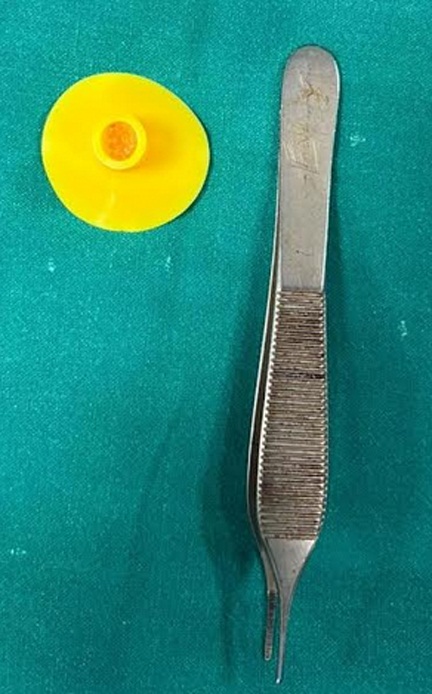

आपातकालीन विभाग में जांच के बाद पता चला कि बच्चे के श्वसन मार्ग में एक सक्शन कप एरोहेड टिप (जो आमतौर पर तीर-कमान सेट खिलौने का हिस्सा होती है) फंसी हुई थी। यह वस्तु बच्चे की जान के लिए सीधा खतरा बन चुकी थी। बिना देर किये उसे पीडियाट्रिक आईसीयू में भर्ती कर स्थिर किया गया और ईएनटी आपातकालीन ऑपरेशन थियेटर ले जाया गया।

वहाँ मुख्य चिकित्सा अधिकारी प्रभारी (चिकित्सा एवं स्वास्थ्य सेवाएं) डॉ. विनीता द्विवेदी के मार्गदर्शन में— डॉ. तनुजा और डॉ. अबानी की एनेस्थीसिया टीम ने अत्यंत नाजुक स्थिति में बच्चे के श्वसन नियंत्रण और एनेस्थेटिक प्रबंधन की जिम्मेदारी संभाली। इस बीच डॉ. अश्विन अशोक जैसवाल के नेतृत्व में (ईएनटी सर्जिकल टीम) की डॉ. प्रियंका, डॉ. रौशन और डॉ. गिरिधर के सहयोग से, डॉ. प्राची मेने के पर्यवेक्षण में बाह्य वस्तु (फॉरेन ऑब्जेक्ट) को सावधानीपूर्वक बाहर निकाला गया। कुछ ही पलों में बच्चे की सांसें सामान्य होने लगीं और माता-पिता की आँखों से राहत के आँसू बह निकले।